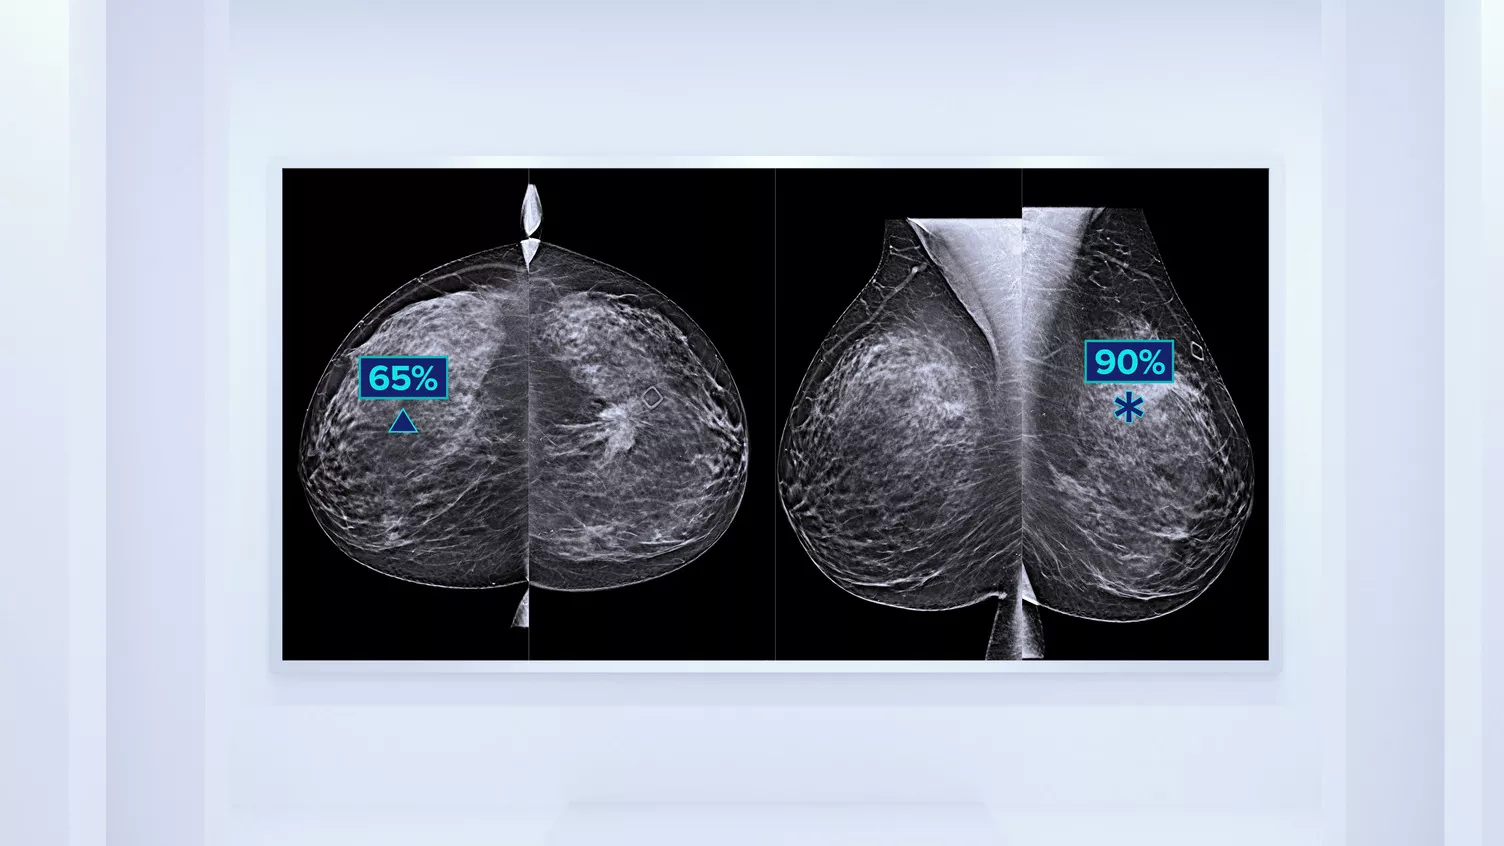

Higher breast density is known to increase a woman’s risk for breast cancer.1 The need for accurate, unbiased analysis is therefore critical. Powered by machine learning, Quantra technology software analyses both 2D™ and tomosynthesis images for distribution and texture of parenchymal tissue. It categorises breasts in four breast composition categories consistent with guidance from the American College of Radiology (ACR) BI-RADS Atlas 5th Edition.2

In addition to volume, pattern and texture of fibroglandular tissue may play just as an important role in mammographic cancer risk prediction.3-5 By analysing and categorising breast texture and pattern, our technology can deliver the accurate information you need to achieve more consistent and reliable scoring and confidently design patient-specific screening.

Objective machine learning algorithm that assigns breast density category based on analysis of breast tissue texture and patterns.